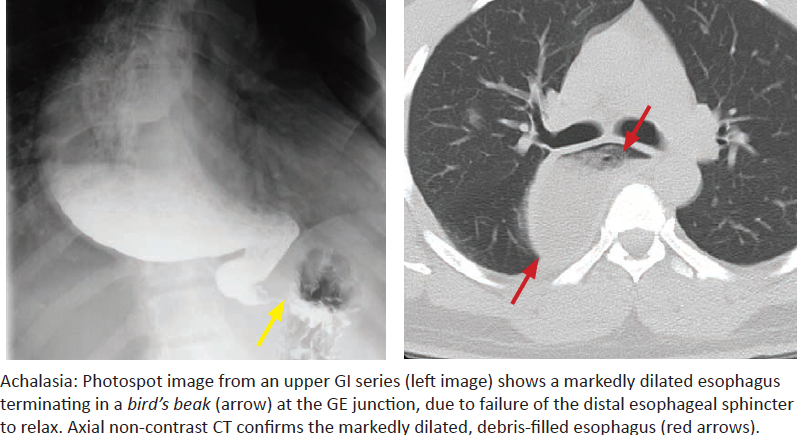

Achalasia

What is it? Why does it happen?

What is vigorous achalasia?

What is a secondary cause of achalasia?

Potential complications?

Classic imaging?

Treatment?

What is pseudoachalasia? How to differentiate?